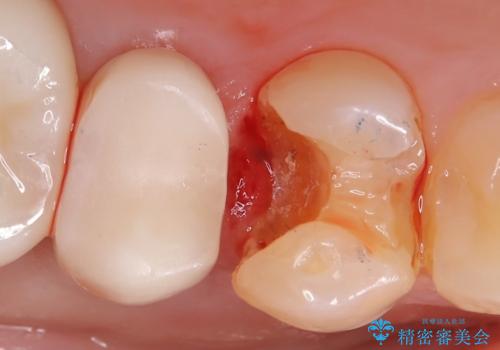

右上4番に歯冠色インレーが入っており、遠心側室エリアのマージン不適を認め、そこに汚れが溜まりやすい状態となっていました。

現在入っているインレー・CR裏層を除去し、再度CR裏層・セラミックインレー形成しました。